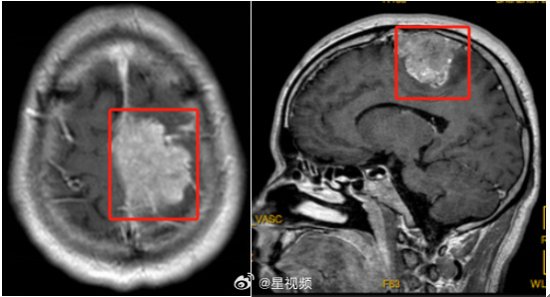

这种情况持续了几个月,王先生的症状越来越严重,整条右腿都使不上劲儿了,于是来到医院就诊。头颅磁共振检查提示左侧顶部颅内脑外实性肿块,压迫上矢状窦。

也就是说王先生的脑袋里长了个矢状窦旁脑膜瘤,直径达到5.6cm。走路会“掉鞋”就是因为肿瘤压迫到了神经,导致肢体偏瘫、感觉障碍。近日,刘诤带领团队成功为王先生切除肿瘤,术后王先生恢复良好,目前已痊愈出院。